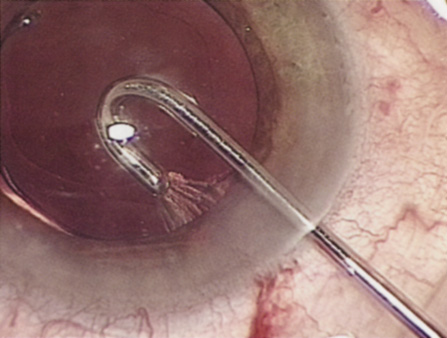

Capsulorrhexis can be performed with a cystitome, capsulorrhexis forceps, or combination-type instruments. Regardless of which instrument is used, several principles can help the surgeon successfully complete capsulorrhexis. It is important to maintain the anterior chamber, because making the chamber shallow increases tension on the zonules and causes the tear to run peripherally. The authors recommend the use of a viscoelastic agent for maintaining chamber depth and, of course, for endothelial protection. Therefore, if the tear begins to run peripherally, the surgeon should redeepen the anterior chamber before attempting to redirect the tear. Additionally, folding the capsule margin can aid the surgeon in redirecting the tear more accurately (Fig. 10).

Fig. 10. The capsulorrhexis tear is more easily redirected by folding the capsule over, in advance of the tear.